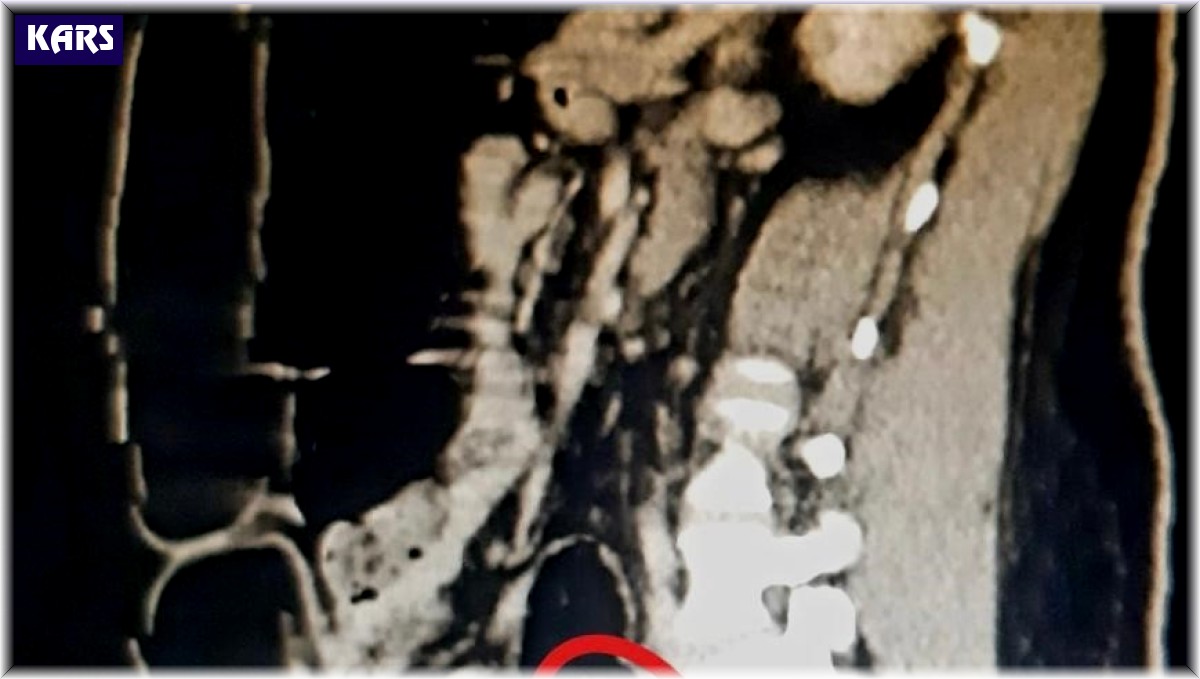

Otobüste gözaltına alınan Hadıs Aeınezad'in yapılan iç beden muayenesinde bağırsaklarında cisim olduğu tespit edildi. Hadıs Aeınezad'ın makadına saklanmış bir şekilde 3 parça 318 gram metamfetamin uyuşturucu maddesi cerrahi müdahaleyle çıkarıldı.